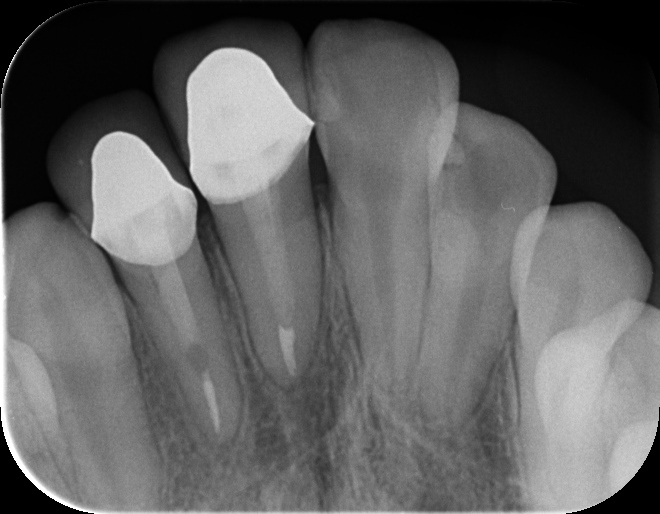

どこがジルコニアかお分かりになりますか?(答えは最後)

正解は右の前歯1番2番です。

土台は歯にやさしいファイバーコアを使用。前歯の虫歯の原因となった、夜間のはぎしりにも考慮して前歯を作りました。

治療内容 フルジルコニアクラウン

性別 女性 18歳

治療期間 5回

治療費 98000円

治療で得られるメリット 審美性

治療の際に起こるリスク・副作用 根管治療の失敗